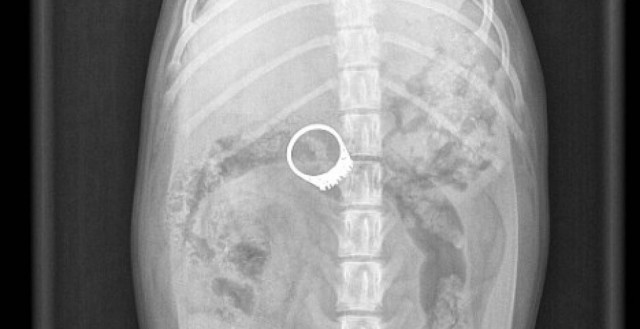

Πού’ ντο, πού’ ντο το δαχτυλίδι…

WHAT THE FACT · 28.02.2011 - 12:33

Για τουλάχιστον τρεις μήνες μία 40χρονη Βρετανίδα από το Νοτινγχαμσάιρ είχε «φάει το σπίτι» της για να...